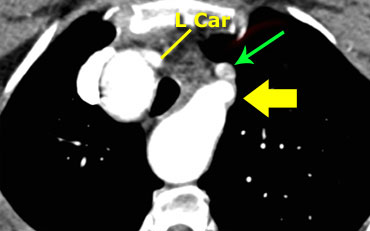

On the left a patient with a right arch with an aberrant left subclavian (indicated by the yellow arrow).

Scroll through the images on the left.

Again you have to realize that the axial CT-images have a ‘view from feet’.

Which vessels are indicated by the yellow and green arrow?

There is a right arch and the left subclavian artery is the last branch of the aortic arch, indicating that this is an aberrant left subclavian.

Medially to the left subclavian artery we see the left common carotid, that originates from the right side and has an oblique course to the left.

The yellow arrow indicates the azygos vein.

The green arrow indicates the left superior intercostal vein, a normal variant, that we will discuss later.